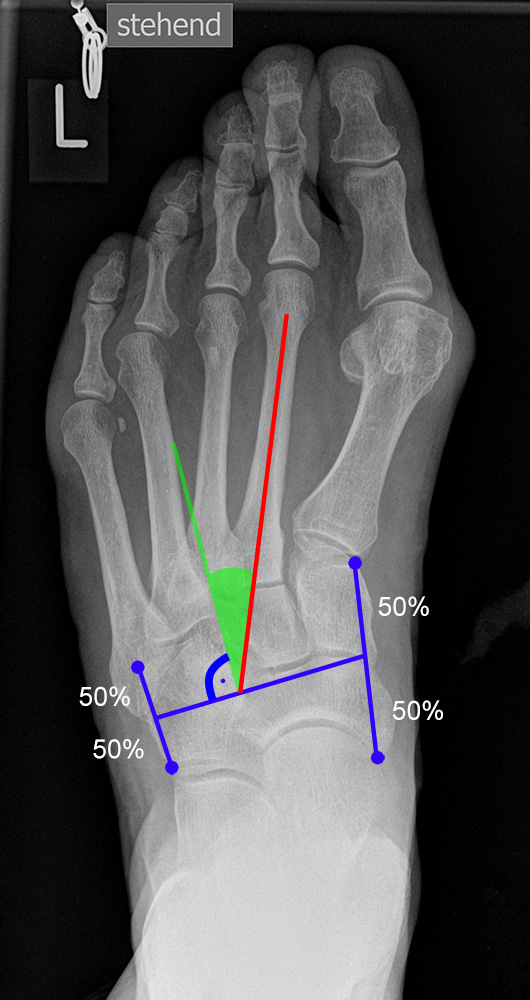

Gelenkflächenwinkel

DMAA (Distal metatarsal artikular angle, Syn. Gelenkflächenwinkel): Winkel zwischen der Achse des Os metatarsale I (rot) und dem Lot auf die distale Gelenkflächenebene (blau) des Os metatarsale I. Die Gelenkflächenebene (grün) wird definiert durch zwei Punkte, welche die mediale und laterale Begrenzung der Gelenkfläche definieren (Norm: <10° 5). Die Projektion des DMAA ist stark abhängig von der Rotation des Os metatarsale I 7. Daher ist bei der operativen Behandlung des Hallux valgus eine Beurteilung häufig erst nach Korrektur der Pronationsstellung des Os metatarsale I möglich. Tendenziell wird der DMAA auf präoperativen Röntgenaufnahmen überschätzt.